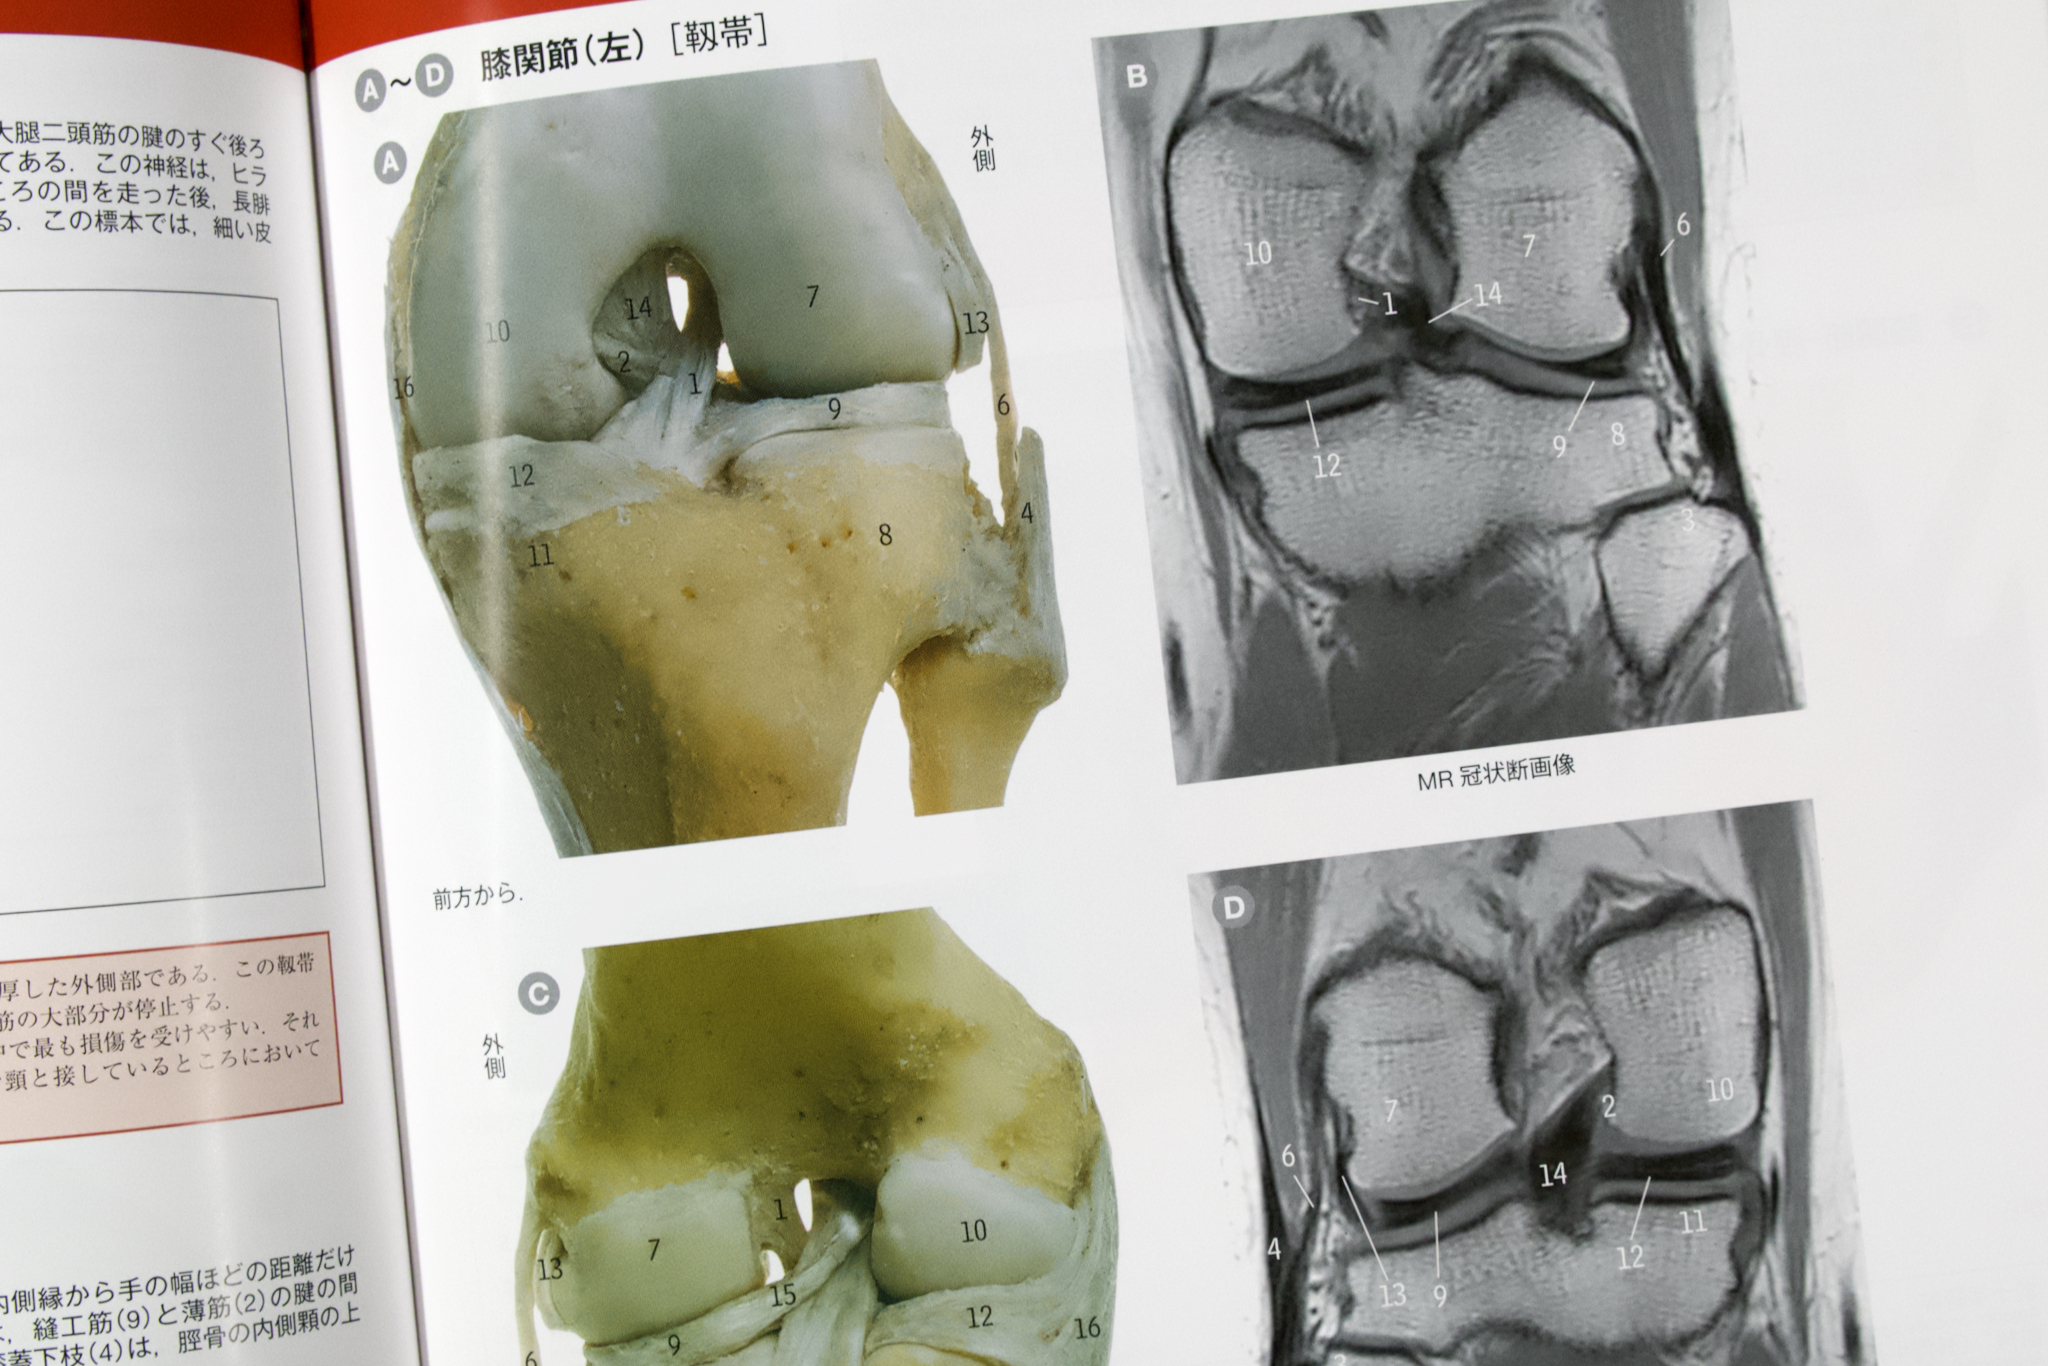

「マクミン」の写真には番号で部位の名称が入っている。これは、「ローエン・横地」と同様だ。「マクミン」ではさらに体表の写真や模式図と解剖体の写真とが対比されていることがおおく、解剖体の構造をみて判別しやすくなっている。

今日では開腹ではなく内視鏡や手術ロボットを使った外科手術が行われることが少なくない。そのようなときにみえる状況を模した写真や、実際の内視鏡手術中の写真も使われる。CT・MRIのような医用画像も解剖体と対比して示される。